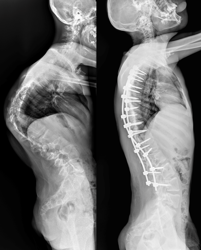

Врачи отделения травматологии и ортопедии РДКБ РНИМУ им. Н.И. Пирогова Минздрава России провели успешную операцию по коррекции кифосколиоза у пациента с синдромом Протея. Хирургическое вмешательство длилось более семи часов и было технически сложным: кифотическая деформация грудного отдела позвоночника составляла более 110 градусов, а комбинированная сколиотическая — по 90 градусов в грудном и поясничном отделах. Благодаря слаженной работе опытной команде хирургов удалось добиться существенной коррекции и обеспечить пациенту достойное качество жизни в будущем. По словам врачей, мальчик даже сможет заниматься своим любимым делом — кататься на велосипеде.

«К нам он поступил с уже существенным искривлением позвоночника. Кифотическая деформация грудного отдела составляла более 100 градусов, а сколиотическая — более 90 градусов в грудном и поясничном отделах. Отмечались нарушения походки, а совокупность этих и других проблем пациента, связанных с основным диагнозом, сильно влияла на его качество жизни», — отмечает Андрей Андреевич .

«Основой вмешательства стала стандартная методика. Дорсальным доступом мы установили транспедикулярные винты (через ножки дуг в тела позвонков), затем при помощи специальных корригирующих маневров постепенно привели деформацию в оптимальное положение и зафиксировали стержнями», — объяснил хирург.

Установленная металлоконструкция получилась достаточно протяжённой: от третьего грудного (Т3) по четвертый поясничный (L4) позвонок. Хирурги постарались сохранить подвижность двух сегментов в нижнепоясничном отделе, чтобы уменьшить степень ограниченности физических возможностей пациента в будущем.

После операции Мурат быстро активизировался и восстанавливался. Хирургам удалось добиться невероятных результатов в коррекции: угол кифотической деформации был снижен до 60 градусов (практически вдвое), а сколиотических — до 40-50 градусов, обеспечен удовлетворительный баланс позвоночника в сагиттальной и фронтальной плоскостях.